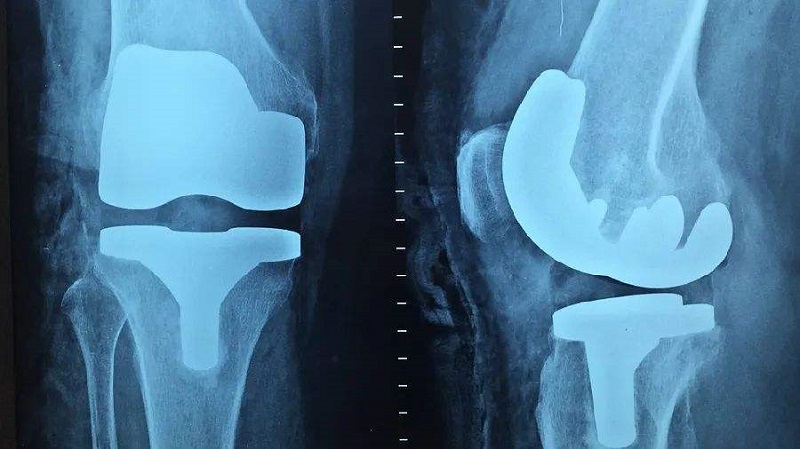

關(guān)節(jié)類植入物產(chǎn)品主要指實現(xiàn)因關(guān)節(jié)周圍骨折、累計關(guān)節(jié)的骨腫瘤及其他原因引起的骨缺損等關(guān)節(jié)障礙的關(guān)節(jié)功能重建的人體植入物,主要產(chǎn)品可分為人工膝關(guān)節(jié)、髖關(guān)節(jié)和肩關(guān)節(jié)以及小關(guān)節(jié)等。